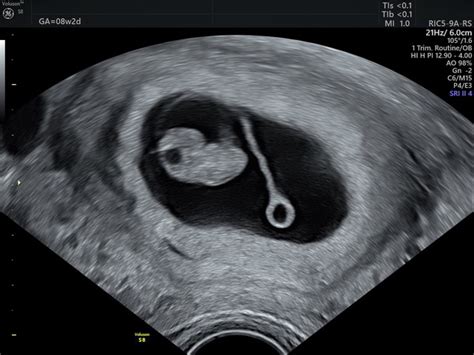

Otrok v tem tednu že razvija sposobnost pogojnih refleksov, kar kaže na razvito možgansko skorjo in spomin. Vse glavne mišične skupine se že odzivajo na dražljaje iz možganov, kar omogoča upogibanje rok v zapestju in komolcu ter stiskanje prstov v pest. Na ultrazvočnem pregledu je morda že mogoče opaziti, kako otrok sesa palec, ter kako se odziva na močno svetlobo od zunaj.

- Spol otroka: V 14. tednu je morda že mogoče ugotoviti spol otroka z ultrazvokom, vendar to ni vedno stoodstotno zanesljivo. Če spola ne želite vedeti, to sporočite svojemu ginekologu pred vsakim ultrazvočnim pregledom.